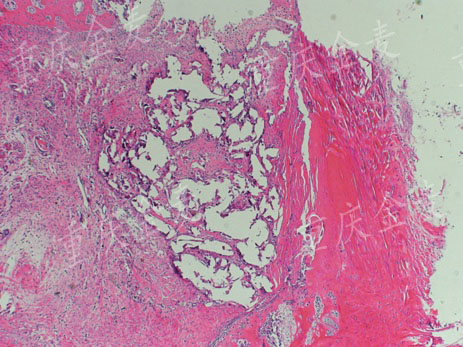

股骨髁外侧缺损4周后H&E染色

股骨髁外侧缺损材料修复4周后H&E染色